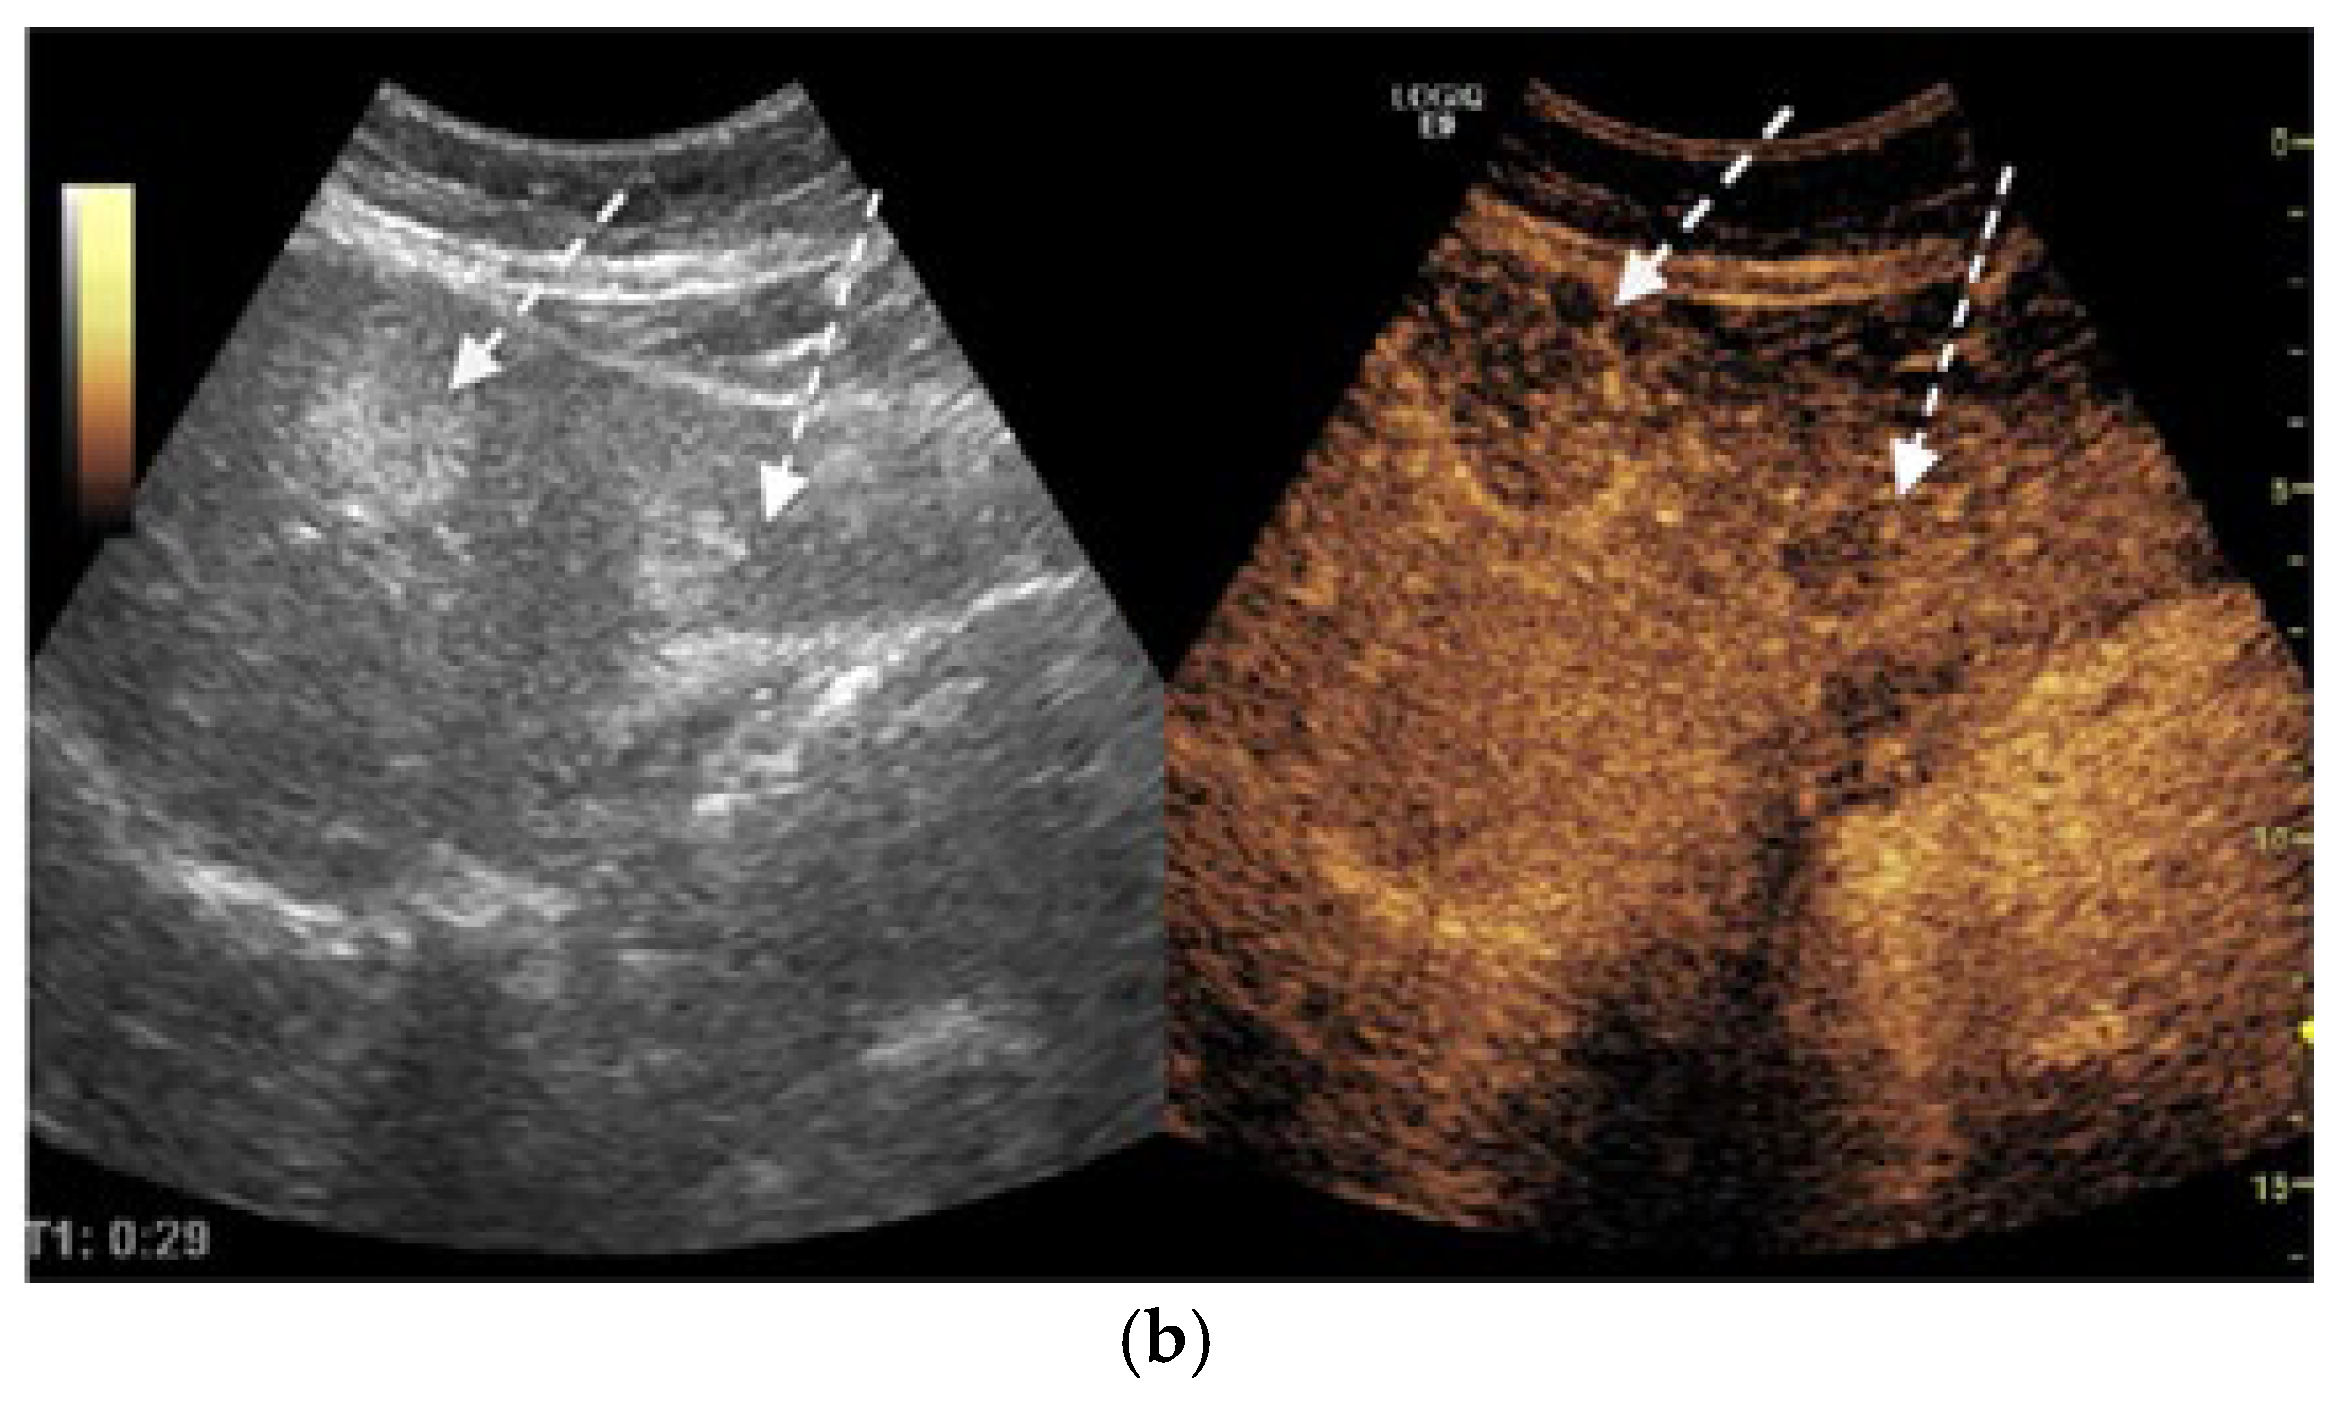

We report the case of a 67-year-old man, presented with intermittent tiredness for about three months, without associated weight loss, fever, or jaundice. The symptom was mild and episodic, occurring several times per week, and not linked to exertion or other systemic complaints. He denied abdominal pain, gastrointestinal bleeding, changes in bowel habits, cough, or flushing. From past medical history we mention chronic hepatitis C virus infection, diagnosed eight years earlier (with liver stiffness 12 kPa on transient elastography). He achieved sustained virologic response (SVR) after treatment with direct-acting antivirals (Sofosbuvir–Ledipasvir). His history also included gastric resection with gastroduodenal anastomosis for peptic ulcer disease 23 years ago, and endoscopic resection of a sessile polyp in the descending colon four years ago, confirmed as a low-grade adenomatous polyp. At the time of presentation, the patient was alert and hemodynamically stable, with vital signs within normal ranges. Physical examination revealed no jaundice, no hepatosplenomegaly, no ascites, or palpable abdominal mass, and cardiopulmonary and neurologic examinations showed no abnormalities. Laboratory investigations were within normal limits, including normal hepatic and renal function. Tumor marker levels—alpha-fetoprotein (AFP), carbohydrate antigen 19-9 (CA 19-9), and carcinoembryonic antigen (CEA)—were also within normal ranges. Abdominal ultrasound revealed three hyperechoic hepatic nodules: the largest, measuring 30 mm, in segment IVa (Figure 1a), with additional lesions in segment III (left lobe) and segment VIII (right lobe). Contrast-enhanced ultrasonography (CEUS) was performed using sulfur hexafluoride microbubbles (SonoVue®), administered as an intravenous bolus of 2.4 mL followed by a 5 mL saline flush. Arterial-phase enhancement of the hepatic nodules was observed at 10 s, with very early washout occurring at 29 s post-injection. This pattern is suggestive of malignant formations, most likely liver metastases (Figure 1b).

Figure 1.

(a) Abdominal ultrasound B-mode image capturing two hyperechoic nodules in left liver lobe (segment IVa and III) with heterogeneous, irregular contours (white arrows). (b) Abdominal ultrasound in CEUS mode at the end of the arterial phase demonstrates earlier contrast washout of both nodules compared to the rest of the liver parenchyma (white arrows).

Diagnosis relies on a multimodal approach, integrating serological test, morphological imaging, functional imaging with histopathological evaluation, and immunohistochemical profiling. Available serological tests for NENs include chromogranin A (CgA), serotonin, 5-hydroxyindoleacetic acid (5-HIAA), gastrin, insulin, proinsulin, C-peptide, glucagon, vasoactive intestinal peptide (VIP), pancreatic polypeptide (PP), calcitonin, adrenocorticotropic hormone (ACTH), somatostatin, and neuron-specific enolase (NSE). [18] Conventional ultrasound often shows strong echoic nodules but lacks specificity. CEUS is more valuable, often revealing a characteristic “fast forward and fast out” arterial hyperenhancement pattern [42]. Hepatic metastases from NENs typically present as hypervascular, ring-enhancing lesions during the arterial phase [17]. However, atypical presentations, such as pseudocystic metastases due to necrosis or hemorrhage, can mimic simple cysts, complicating diagnosis [16]. CT and magnetic resonance imaging (MRI) are standard imaging modalities for the detection and characterization of both primary neuroendocrine tumors and associated liver metastases. In our case, CT scan not only confirmed the presence of hepatic lesions but also identified an additional tumor site in the mediastinum. Functional evaluations are used to detect somatostatin receptor expression on tumor surfaces. Common techniques include 68Ga-DOTATATE PET, 64Cu-DOTATATE PET, 68Ga-OTATOC PET, and PET-CT with fluorodeoxyglucose for non-functional lesions [9,18]. These imaging methods are invaluable for staging, identifying the primary tumor, and guiding treatment decisions [43]. A limitation of this case report is the absence of functional nuclear medicine imaging, such as 68-Gallium-DOTATATE PET/CT and 18F-FDG-PET/CT. While these examinations are integral to the staging and characterization of many neuroendocrine neoplasms, the decision to forego them was made deliberately by the multidisciplinary team.